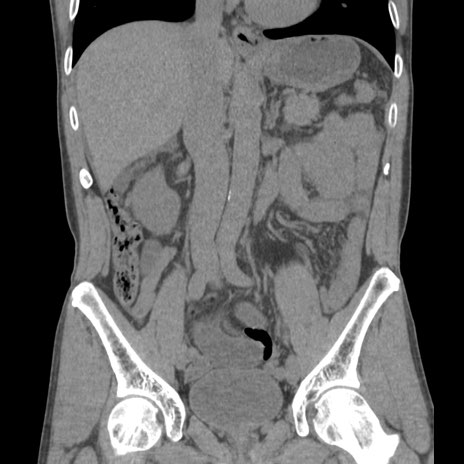

症例56 CT(冠状断像)

脂肪ウインドウ